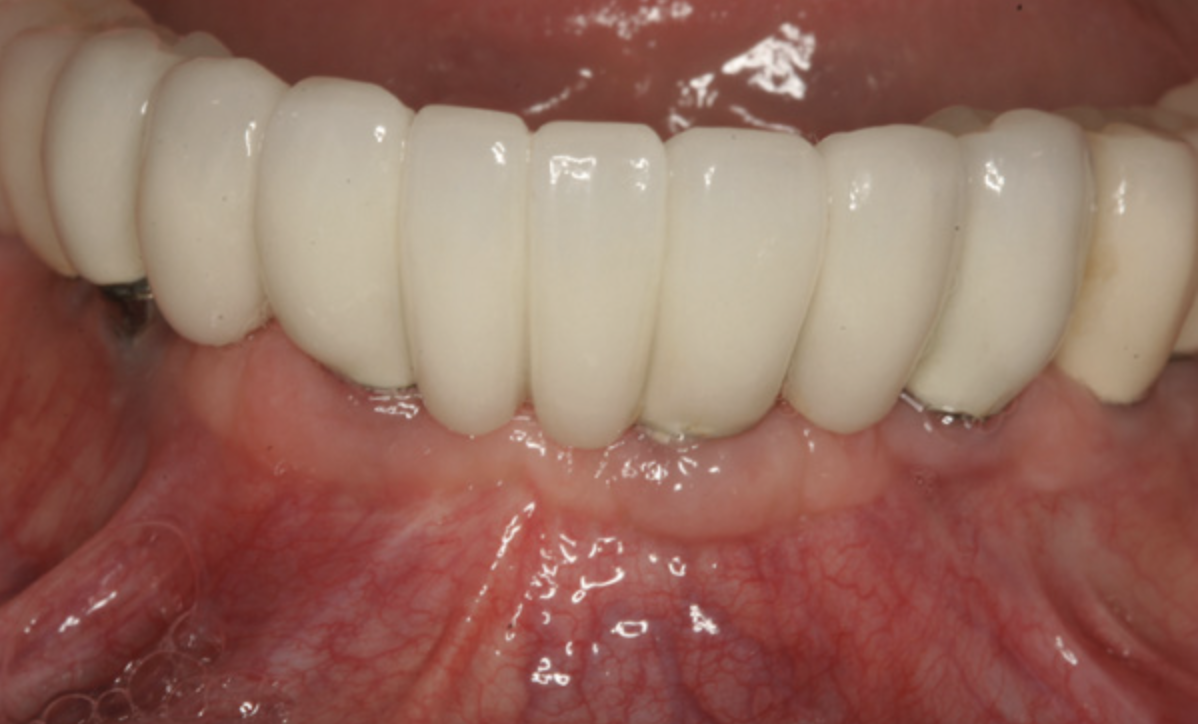

Fig 2. Patient in Figure 1 who received BPCS graft shown 5 years after prosthetic loading of the implant.

Figure 2

The patient shown in Figure 1 had presented after significant endodontic-related abscesses reduced the height of both buccal and lingual plates of bone. Covering the biphasic calcium sulfate (BPCS) graft with a dense polytetraflouroethylene (PTFE) barrier for 3 weeks enhanced healing in the site. Clinically, it is apparent that the ridge volume was maintained over 5 years and supported keratinized tissue (Figure 2). Most importantly, there was, on histologic evaluation, 58% vital bone, with no remnants of the bone replacement graft material (Figure 3).